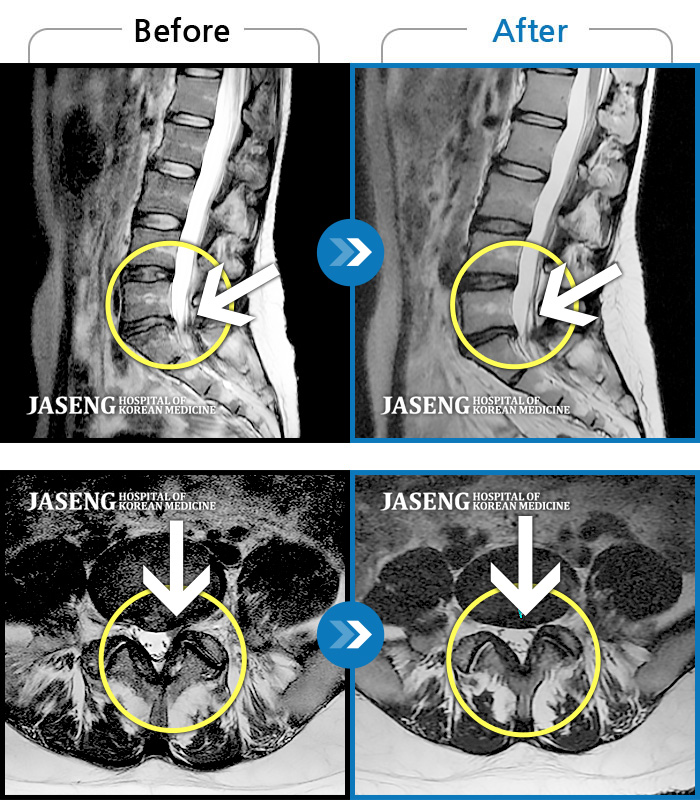

허리디스크

보라매 · 왕오호 원장

허리와 좌측 엉치 통증

촬영시기

2015.12.29 ~ 2018.10.11

2018.12.28